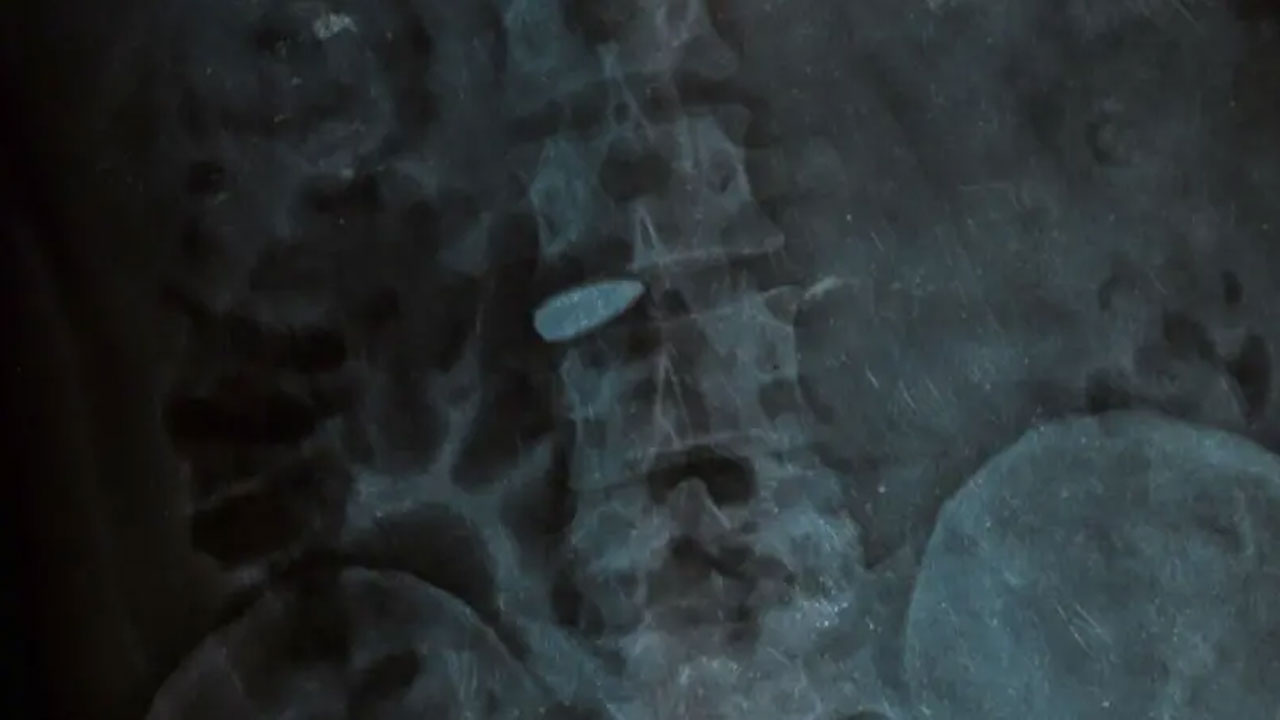

মেরুদণ্ডে আটকে আছে বুলেট

শাকিল সেদিন প্রাথমিক চিকিৎসা নেন গাজীপুরের স্থানীয় একটি হাসপাতালে। সেখানে এক্স রে রিপোর্টে ধরা পড়ে যে কোমরে মেরুদণ্ডের হাড়ে বুলেট আটকে আছে।

শাকিল পরে চিকিৎসা নেন বিএসএমএমইউতে এবং পরে সিএমএইচ-এ। কিন্তু সবখানেই জানানো হয়, এই বুলেট ‘বের করা যাবে না’।

“মেরুদণ্ডে এমনভাবে আটকাইছে বুলেটটা যে এটা বের করতে গেলে আমি মারা যাইতে পারি। অথবা পেছনের অংশটা প্যারালাইসিস হয়ে যেতে পারে। সব হাসপাতাল এইটাই বলছে। যেভাবে আছে সেভাবেই রাখতে হবে আপাতত। আর এটার চিকিৎসা নিতে হলে দেশের বাইরে যেতে হবে। কিন্তু সেটা তো আমার পক্ষে সম্ভব না। আমার সেই সামর্থ্য নাই।”